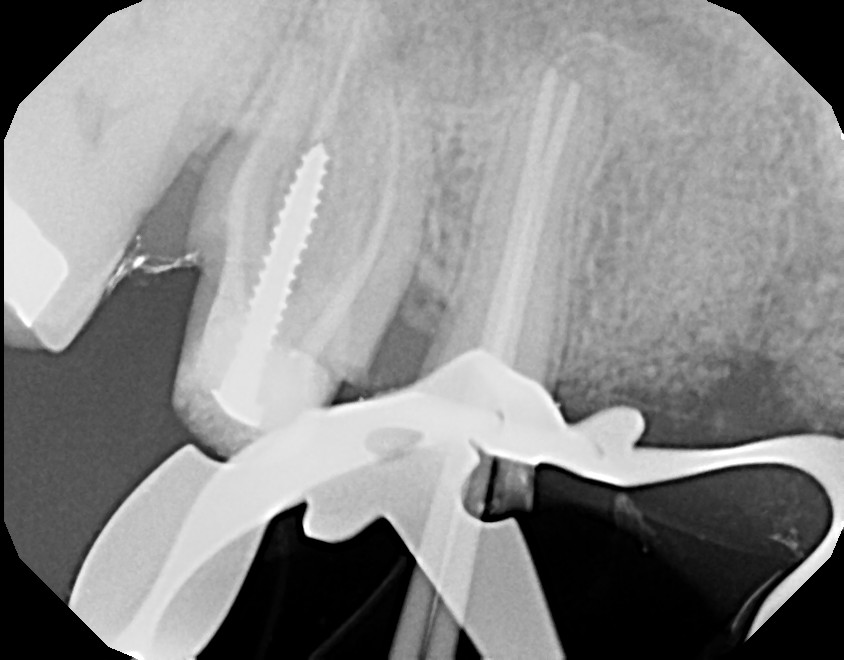

This is a root canal retreatment procedure of 2nd maxillary premolar (tooth #4) due to a missed canal which caused infection. An additional canal was located, both canals were retreated and the tooth will be restored with a crown. The first maxillary molar (tooth #3) needs to be retreated (redone) as well because of infection, due to inadequate root canal therapy. Always ask your general dentist for a referral to an endodontist (root canal specialist) for your root issues.